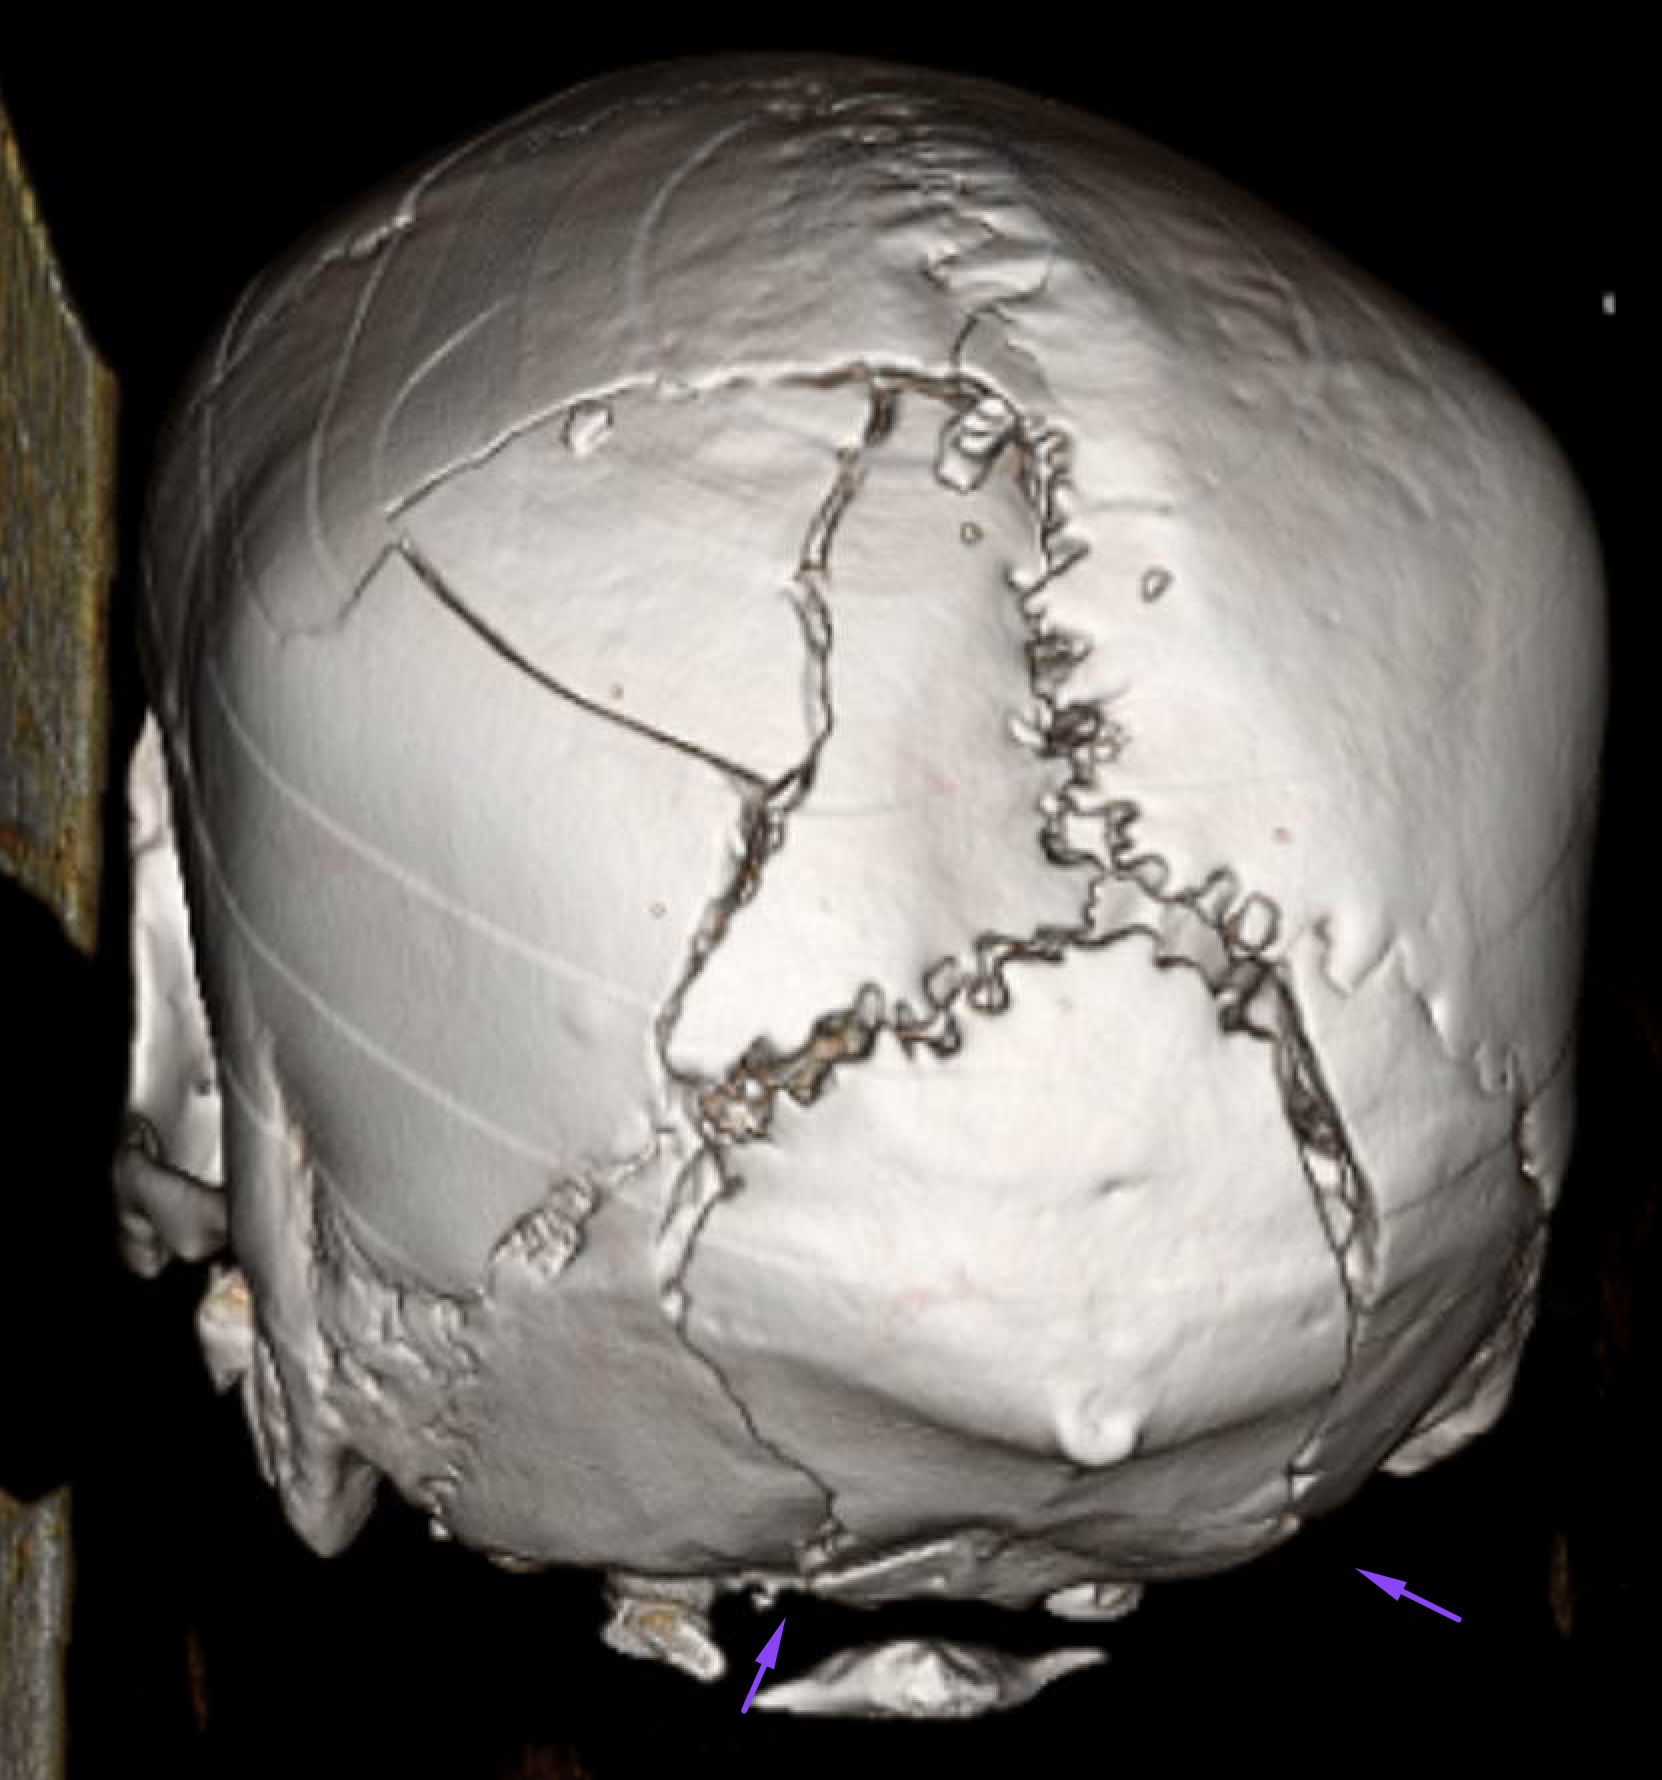

Age: Unknown

Sex: Male

Indication: Evaluate for brain death, trauma patient

Radiotracer: Tc99m ECD (ethyl cysteinate dimer)

Sample ReportNo evidence of intracranial perfusion. While not diagnostic in itself, this finding would support a clinical diagnosis of brain death.